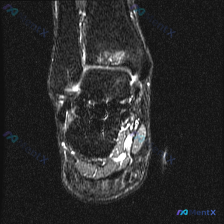

踝关节MRI看到骨髓水肿+腱鞘积液,这个病例容易只想到扭伤,鉴别诊断要扩得开

刚整理完一份踝关节MRI的读片分析,这个病例挺有代表性,影像表现不算复杂,但鉴别诊断很容易漏严重问题,分享给大家一起看看。

这是一张踝关节的冠状位T2加权压脂MRI,我们来逐层梳理异常:

- 骨骼: 距骨体内可见局限性斑片状不均匀高信号,提示骨髓水肿;胫距关节间隙可见少量高信号,提示轻度关节积液

- 软组织: 内踝下方(三角韧带区)软组织可见弥漫异常高信号,边界不清,提示水肿或损伤;外侧结构相对清晰,仅少量周围软组织高信号

- 肌腱腱鞘: 足底内侧、距骨下方的多条肌腱(胫骨后肌腱、趾长屈肌腱等)周围可见明显高信号液体影,符合腱鞘积液(腱鞘炎)表现

第一眼看去,三个核心异常:距骨骨髓水肿 + 内侧软组织损伤水肿 + 多肌腱腱鞘积液,这种组合最容易想到的就是踝关节扭伤后的继发改变,不管是内翻还是外翻扭伤,都可能出现这种应力性的改变。

但这个表现并不是创伤特有,我们必须把鉴别诊断铺开,不能直接锚定在扭伤上。